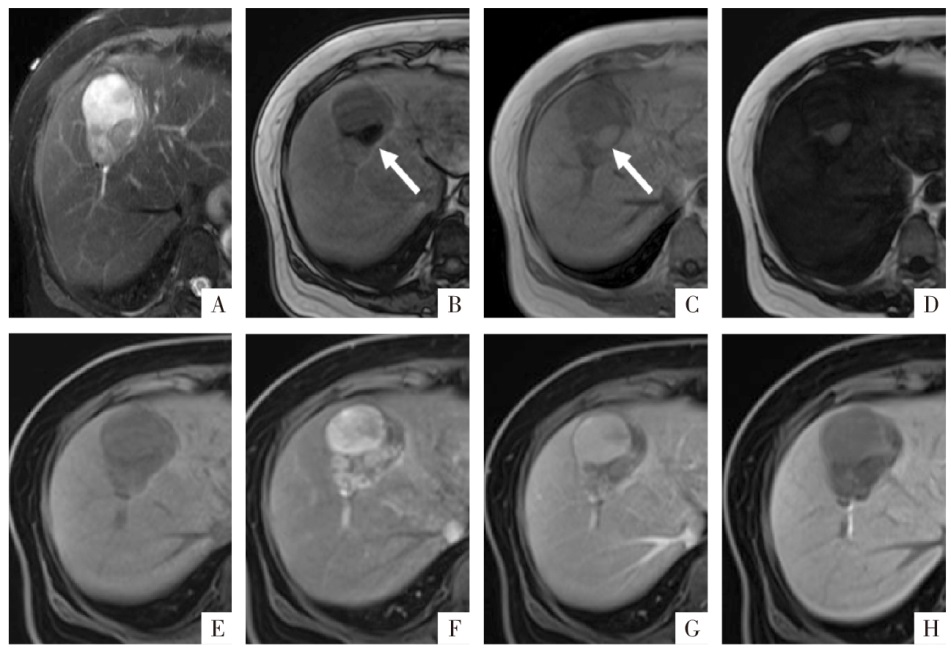

图8

病人女,63岁,发生脂肪变性的肝细胞癌。A图,T

2

WI上显示肝S8段轻中度高信号肿块。B、C、D图分别为同相位、反相位及脂像,反相位见一信号减低区域(白箭),相应区域在脂像呈明显的高信号,为病灶内的脂肪变性。E—H图分别为钆塞酸二钠增强扫描蒙片、动脉期、门静脉期及肝胆期影像,见非周边的动脉期高强化、廓清,病灶整体在肝胆期的信号要低于周围肝组织。